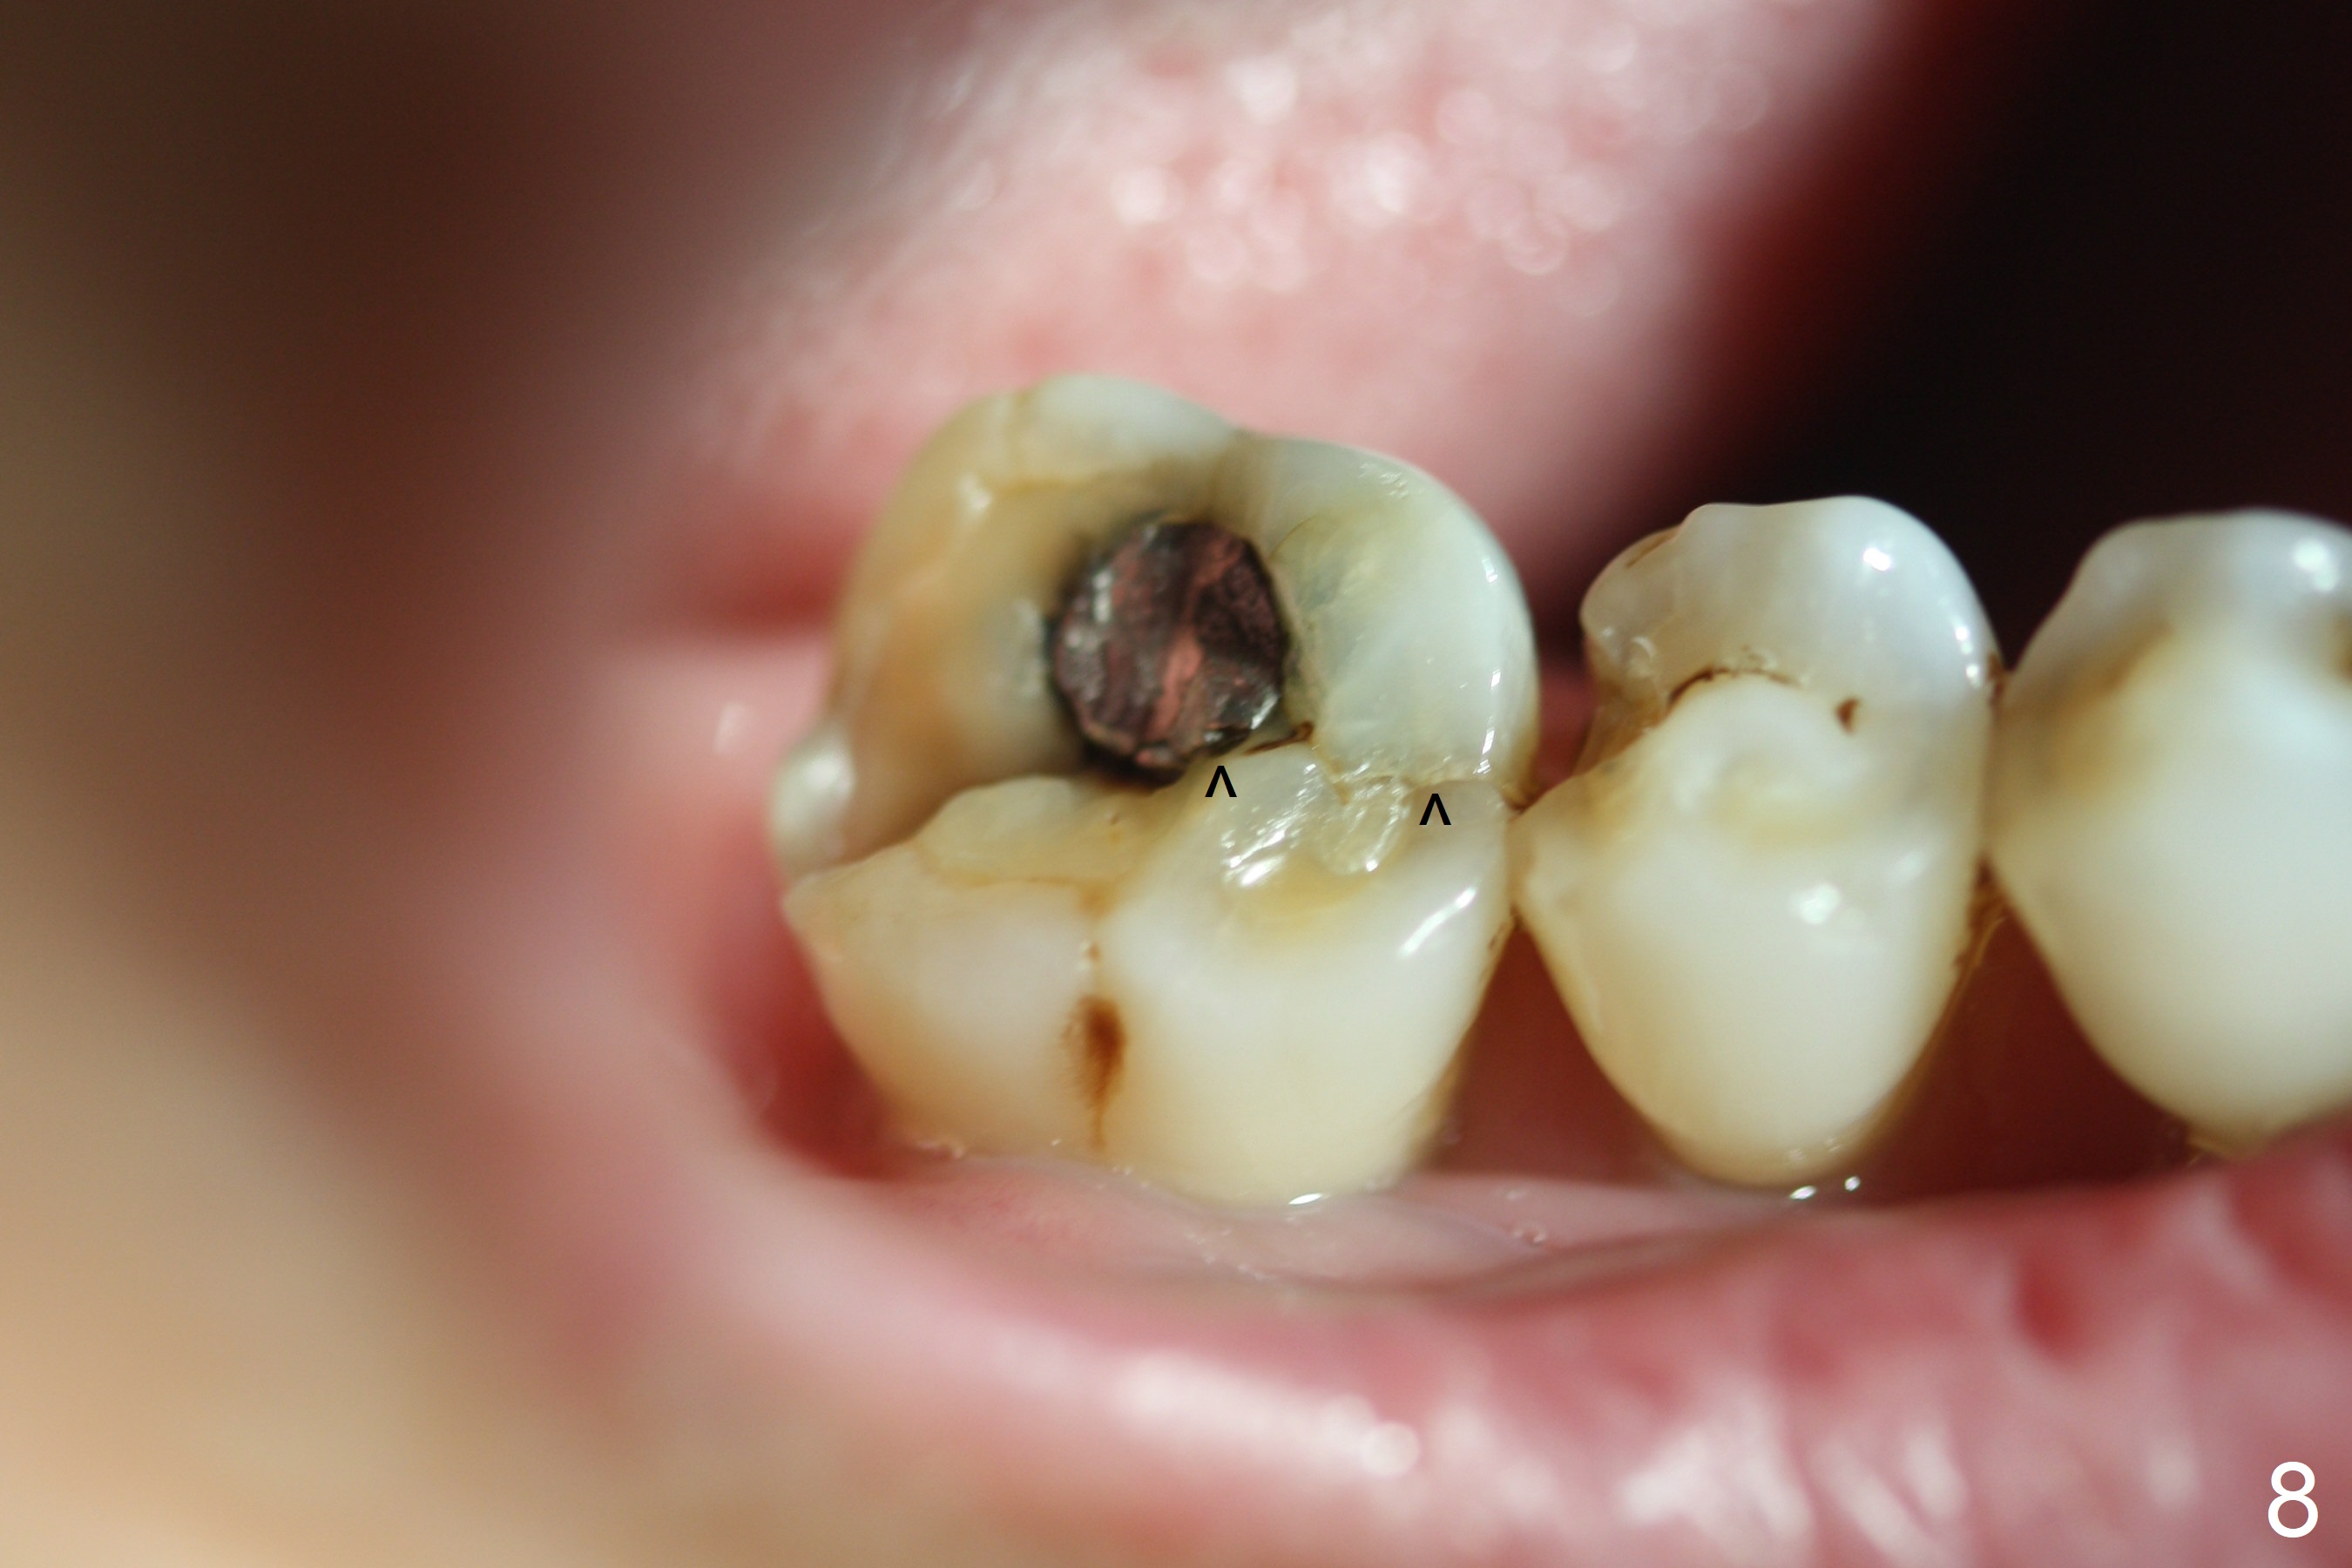

A 71-year-old woman (bruxer) wants to remove the tooth #30 (occlusal trauma, possible root fracture) for implant following the one at #14 (Fig.1). IBS abutment screw tends to loosen in functioning if the implant is placed too deep and/or off the longitudinal axis. If these two conditions are not controlled well, switch to a large tissue-level implant. A drawback of placing the implant in the septum is that the mesial margin of the abutment (Fig.2 pink) is subcrestal. If the implant is placed in the mesial socket (Fig.5 red line), the imagined abutment margin plane (white line) is parallel to the mesiodistal crests. Initial osteotomy entry point in the mesial socket and trajectory should be adjusted intraop (compare Fig.6 and 7) so that the apex of the implant will not be too close to the apex of the tooth #29 (to avoid truncating the neurovascular supply to the tooth (Fig.6 red arrowheads)) at the same time the abutment inclination is not too compromised (Fig.7). To prevent pressure upon the buccal (Fig.4 B) plate, osteotomy should be slightly lingual and/or the diameter of the implant is to be < 7 mm. Use a 3 mm unipost for provisional and probably 5 mm one for definitive restoration. Apply bonding to the post if the implant is 6 mm or less. The provisional margin should be wide and deep for deep margin and easy impression later. Use IS drills with 4 mm stopper for osteotomy if the septum is absent. Prepare Rongeur and surgical handpiece to remove the remaining septum if needed. Be wary of the distally curved root tip of #29. In fact there is a mesiodistal crack line (Fig.8 arrowheads) with buccal recession (Fig.9, 2 weeks preop).